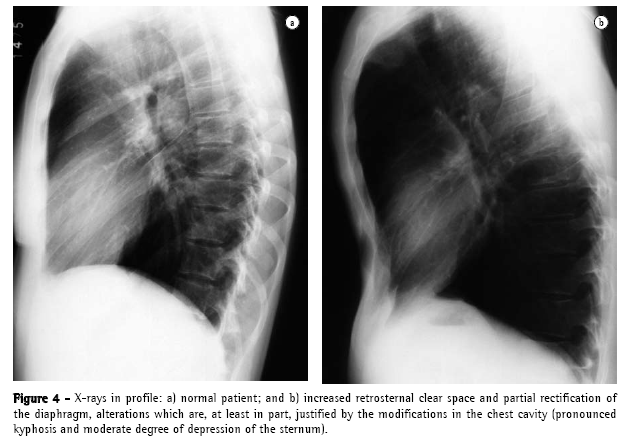

The yield of conventional chest X-ray in the evaluation of emphysema is quite limited. When there is no significant air trapping, the principal alteration is reduction of vasculature, which is only perceived too late in the natural history of the disease, and is an extremely subjective criterion. When there is air trapping (Figures 3 and 4), the criteria are safer, and can be divided into 3 basic groups of alterations,(6,8) presented in Chart 1. When all criteria are present, the diagnosis is definitively confirmed. It should be noted that the increased right chambers of the heart, with reduction of the intrasegmental vasculature, can also be identified in pulmonary arterial hypertension, without emphysema. It should also be noted that bullae are only present in approximately one-third of the cases.

Considering that the hemidiaphragm has a surface of approximately 250 cm2, we can calculate that each 4 cm dislocation of the diaphragm determines a dislocation equivalent to approximately 1 L of volume in each lung (2 L, if we consider both lungs). When there is air trapping, the mobility of the diaphragm is limited during expiration. End-expiratory pulmonary volume is significant in the recognition of emphysema. In general, the dislocation of the diaphragm between maximum inspiration and expiration ranges from 3 to 10 cm, corresponding to volumes ranging from 1500 mL to 5000 mL. Cranial dislocation <2 or 3 cm during expiration indicates limited diaphragmatic excursion in the individual with emphysema.(21)

One author comments that the emphysematous pattern defined by the conventional radiological study is only present when the emphysema is so pronounced from the anatomopathological point of view that, in general, pulmonary reserves have already been depleted or pushed to the limit (6,8) A more updated review(22) confirms these propositions:

"If the lungs are mildly affected by emphysema, the X-ray is frequently normal";

"Emphysema can be diagnosed by X-ray when the disease is advanced"; and

"Only half of the patients with emphysema of moderate extent can be diagnosed by chest X-ray."

Both authors suggest that conventional chest X-ray is not a reliable method for the diagnosis or quantification of emphysema.(22) This limitation is so significant that some authors(21) demonstrated that, when conventional radiology managed to diagnose chronic obstructive pulmonary disease, 53% of the patients died within 5 years, and 70% died within 10 years.